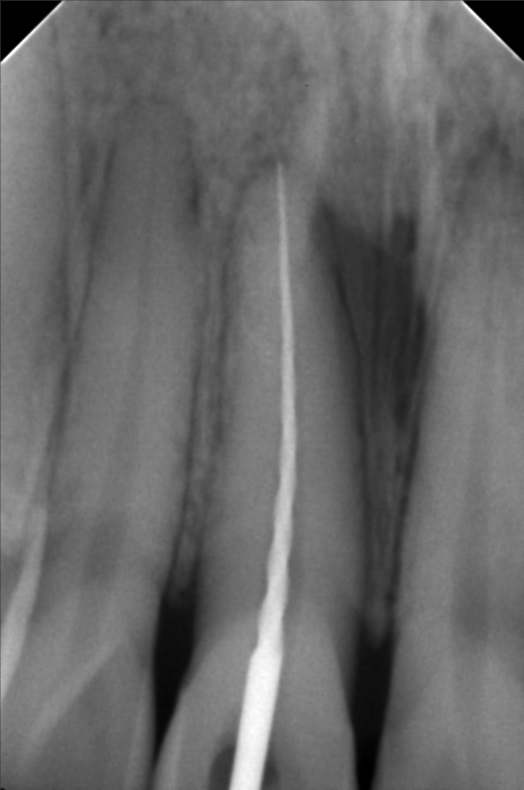

Edit Record Check our patient data records. Add patient information Patient Info Profile picture Last Name First Name Middle Name Birthdate Age Street Barangay City Country Zip Code Contact number Email Procedure 07/31/21 adj 16x22 UL 09/24/21- removal of lower braces exo 46/ upper adjustment chain 10/23/21- removal of braces upper and lower (for resto: 36/37/47 RCT #11- open canal 26mm= camphenol 11/3/21- 26mm yellow and white file apexcal composite veneer #11 11/08/21 - red file/ laser RCt tx for obturation next meeting 11/13/21 - obturation 26mm with restoration lingual pit 03/5/22- LC 26 Lingual pit, Occ/ Op File icalabisrct11.jpg File 2 301088955_824076712092412_6089268001725499639_n.jpg File 3 301583710_588567209482622_936847165020659250_n.jpg File 4 301875545_1490603051363326_3867455551585293159_n.jpg File 5 302308769_1073326889984866_975291161993186277_n.jpg File 6 File 7 File 8 File 9 File 10 File 11 File 12 File 13 File 14 File 15 File 16 File 17 File 18 File 19 File 20 Retain Record Retain Record Yes No Save Your Changes